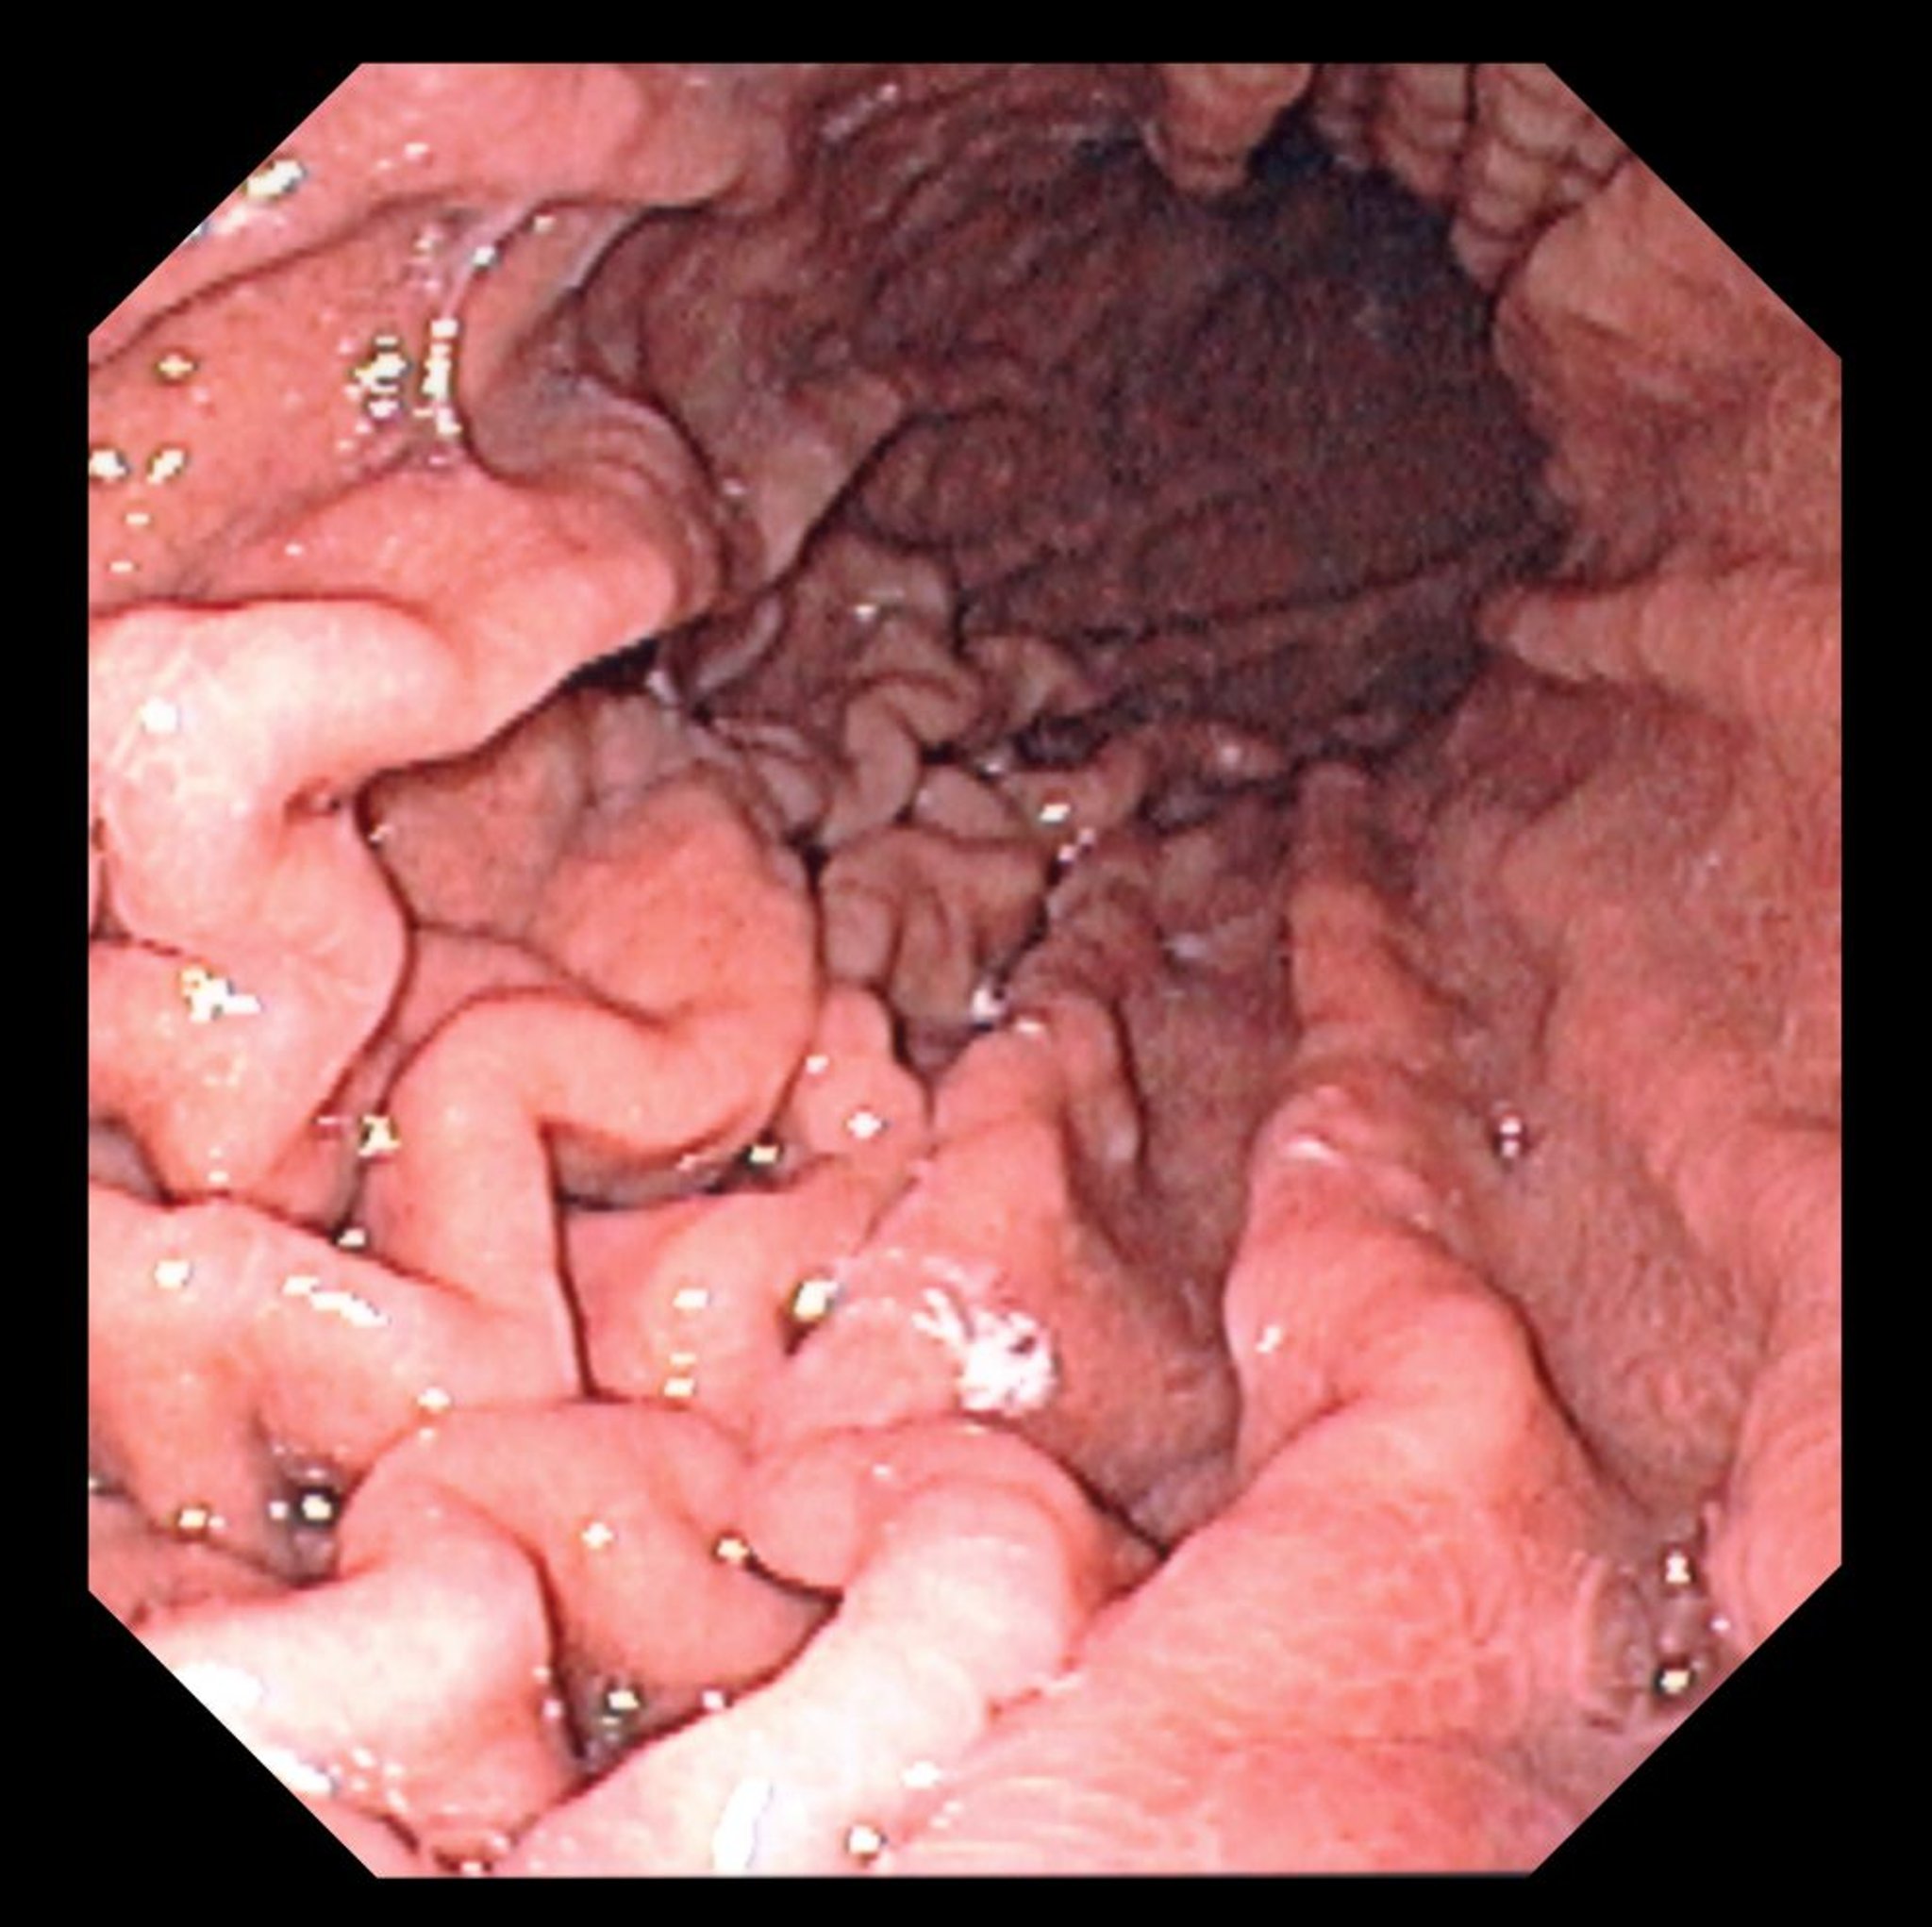

Esta foto mostra uma visualização endoscópica do fundo do estômago normal com pregas gástricas características.